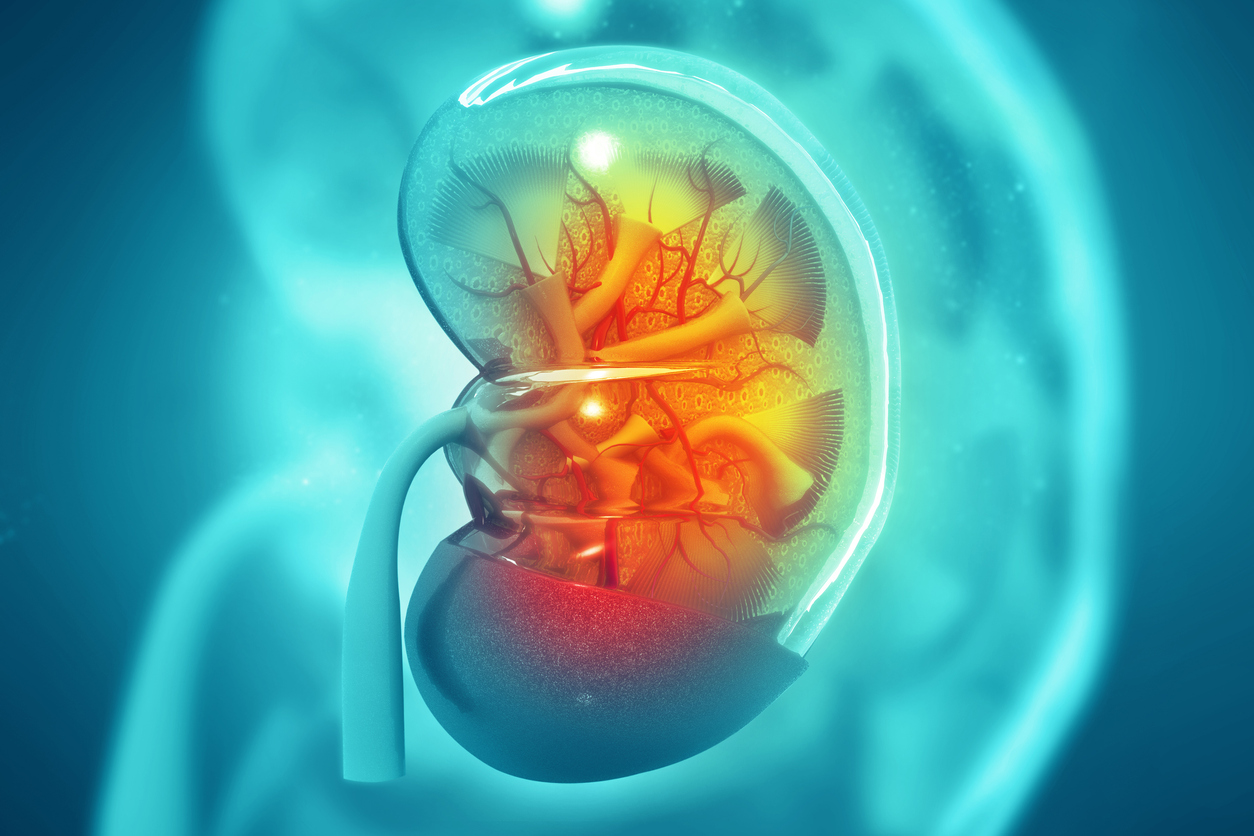

Οι νεφροί αποτελούν μέρος του ουροποιητικού συστήματος, το οποίο εξαλείφει τα απόβλητα και την περίσσεια υγρών και ηλεκτρολυτών από το αίμα. Επίσης ελέγχουν την παραγωγή ερυθρών αιμοσφαιρίων και ρυθμίζουν την αρτηριακή πίεση. Οι καρκίνοι των νεφρών προέρχονται κυρίως από δύο μέρη του νεφρού, τον νεφρικό σωλήνα και τη νεφρική πύελο.

Περίπου το ένα τέταρτο (24%) των περιστατικών καρκίνου του νεφρού συνδέεται με το υπερβολικό σωματικό βάρος και άλλο ένα 24% συνδέεται με το κάπνισμα. Η έρευνα έχει διαπιστώσει ότι ο κίνδυνος καρκίνου των νεφρών είναι 23% υψηλότερος ανά 10 εκατοστά μεγαλύτερου ύψους στο άτομο. Ο κίνδυνος είναι επίσης υψηλότερος σε άτομα με διαβήτη.